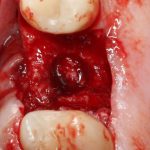

Кстати, обрати внимание на ширину альвеолярного гребня (левая картинка). Она чуть меньше 3 мм. Это объясняет, почему я засомневался в возможности установки имплантатов одновременно с остеопластикой. Понятно и без КЛКТ.

Наперво, мне нужно удалить разрушенный зуб и получить костный аутотрансплантат.